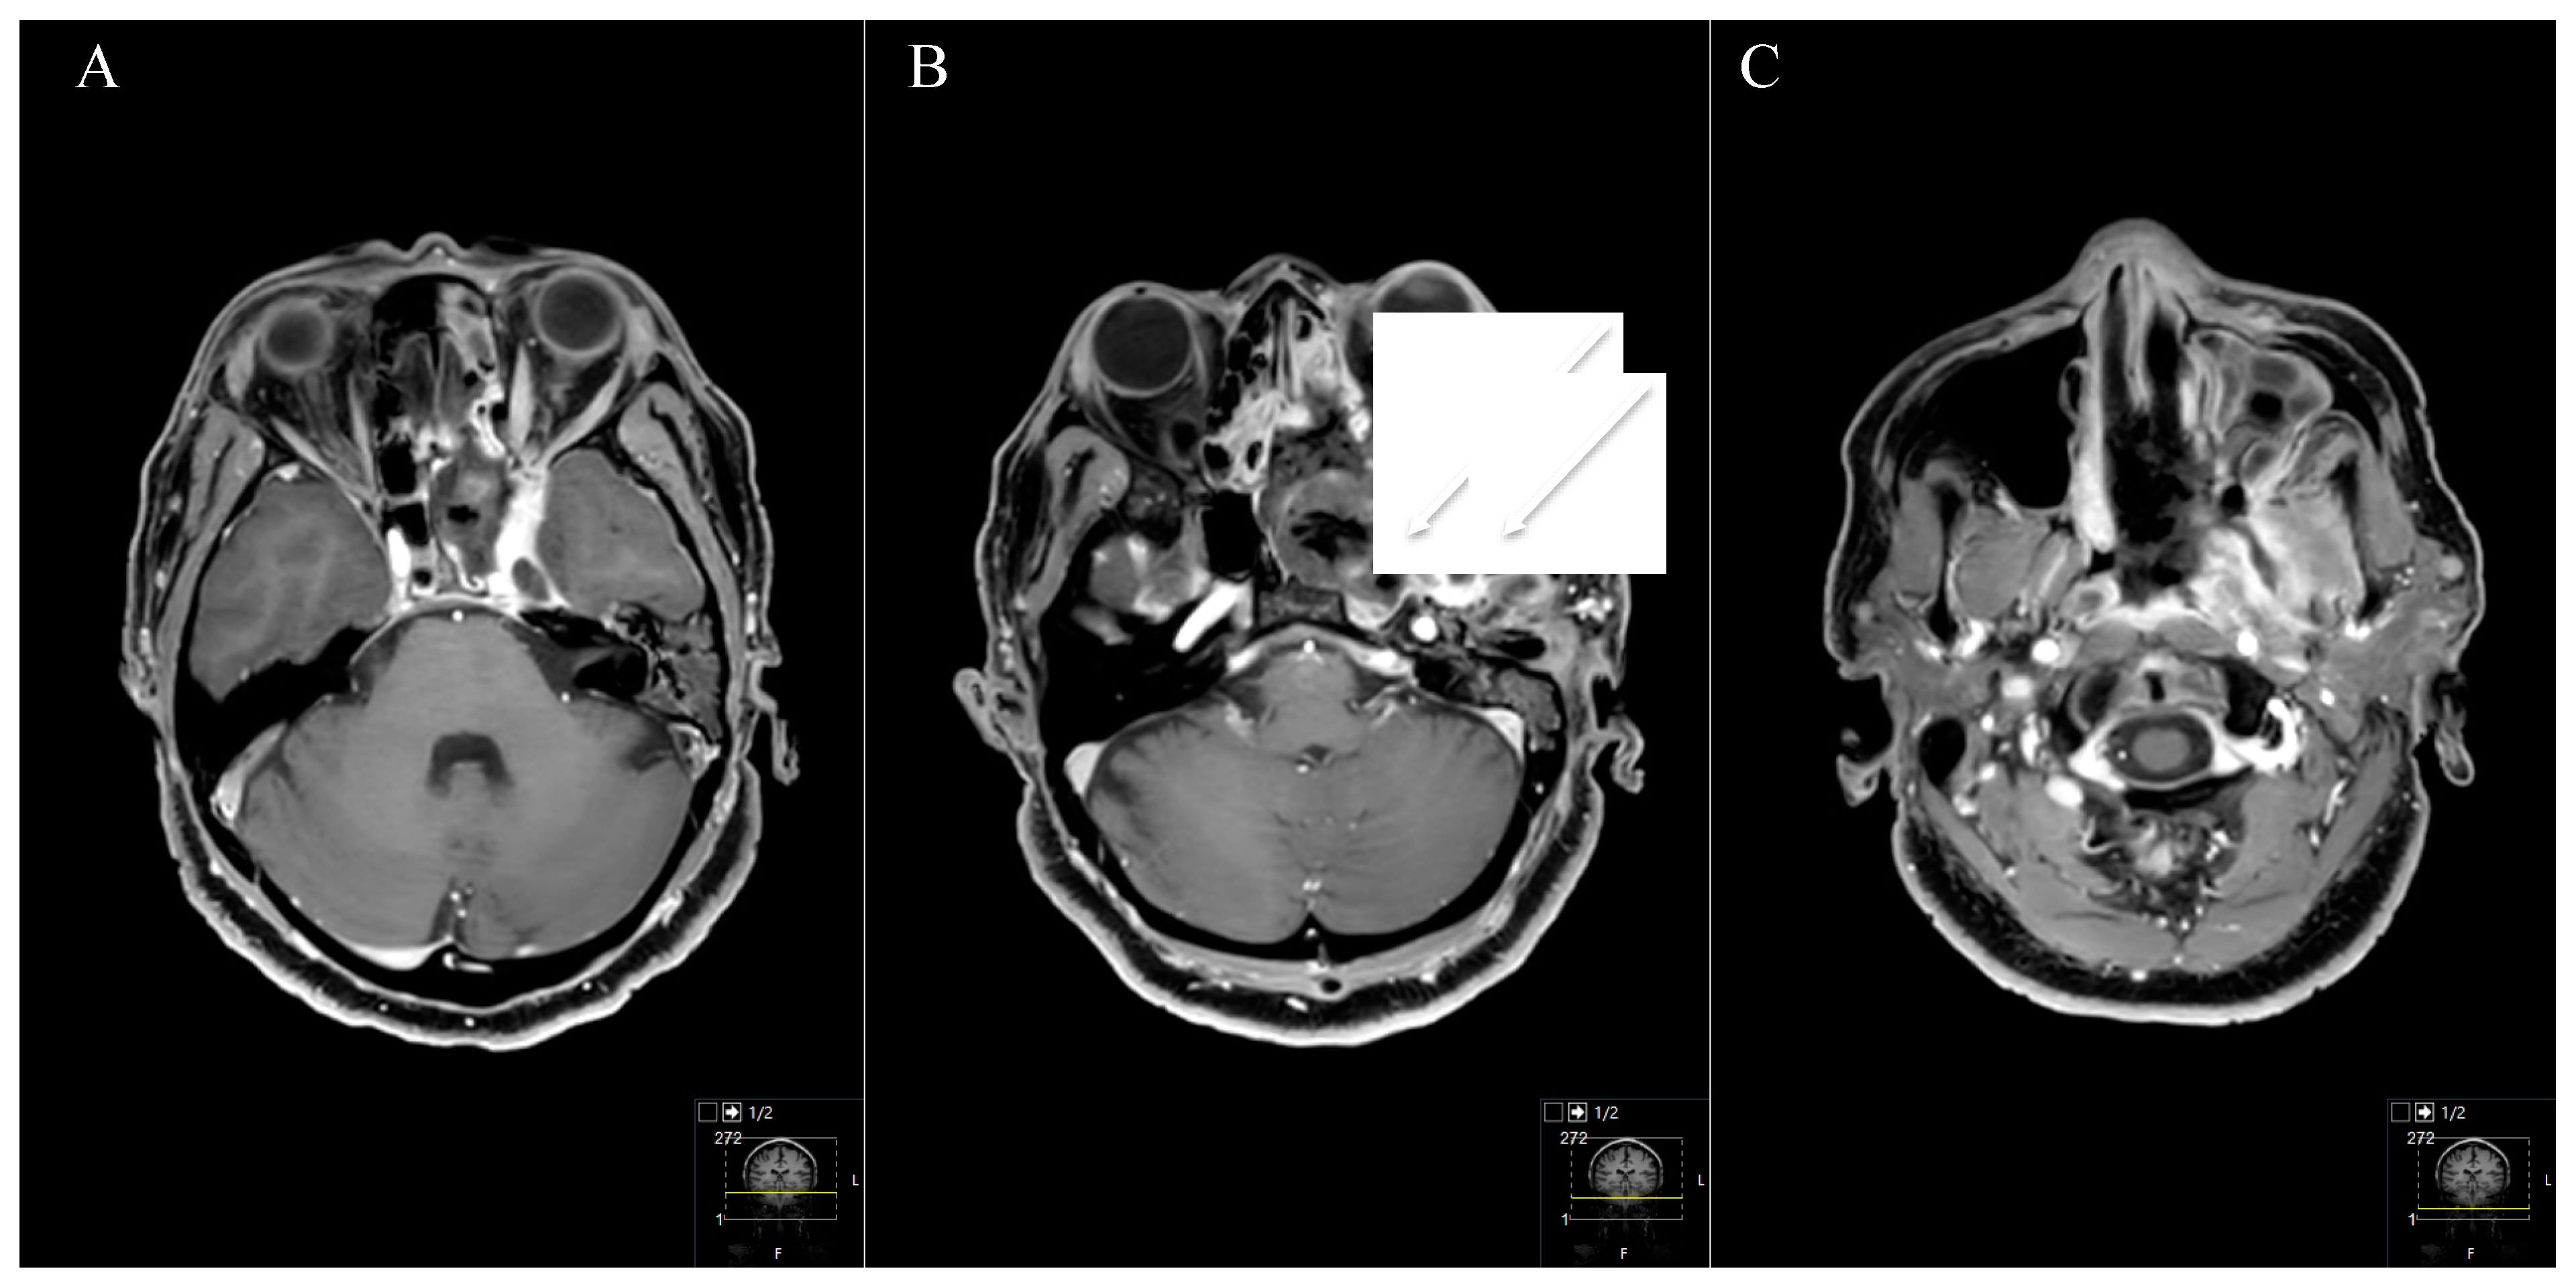

Different classifications have been described in the literature [3,4,5,6,7]. Samii et al. proposed a simplified and useful division into four categories based on radiological findings, whereas Ramina et al. added modifications according to the level of difficulty, describing also two-stage approaches for the most difficult so-called “Type F” tumors [5,6] (Figure 2).

Tumour locations were classified according to Samii’s and Ramina’s classification [5,6]. According to Samii et al. (Table 2), six schwannomas were classified as Type A, two as Type B, four as Type C and one as Type D. In two cases, the tumor was resected in a two-stage technique. The intradural subtemporal approach was performed in five cases, the extradural technique once, the retrosigmoid in five cases, the Kawase and a transnasal approach in two cases, respectively. The two cases with a two-stage approach (one neurofibromatosis type 2 (NF2) patient, Figure 1) were classified as Type E, according to Ramina et al., reflecting the surgical difficulty [6].

Treatment strategy for trigeminal schwannomas should always respect the individual’s anatomy, clinical presentation and the patient’s baseline characteristics. As already described, diverse classifications have been proposed to facilitate decision making and assess the technical difficulty [3,4,6,11,20,21,22]. However, we believe the choice is mainly whether the tumor has to be approached via a posterior or a middle/anterior fossa approach. Thus, the basic division made by Samii et al. puts the options in a nutshell with following classification [5]: Type A, intracranial tumor predominantly in the middle fossa; Type B, intracranial tumor predominantly in the posterior fossa; Type C tumors in the middle and posterior fossa and Type D extracranial tumor with intracranial extensions.

Figure 8. Illustration displaying surgical techniques and outcomes for each tumor type (according to Samii). STA = Subtemporal approach. TNA = Transnasal endoscopic approach. RSA = Retrosigmoid approach. GTR = Gross total resection. STR = Subtotal resection.